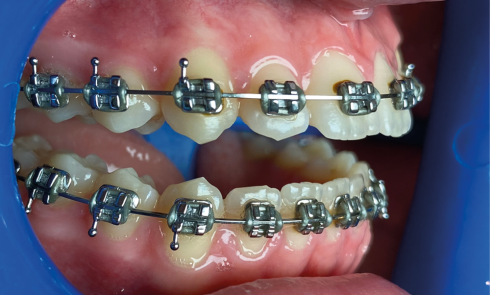

Article réservé à nos abonnés Débaguage et polissage

Questions Quelles sont les étapes du nettoyage ? Quels sont les risques pour l’émail lors du débaguage ? Existe-t-il une...